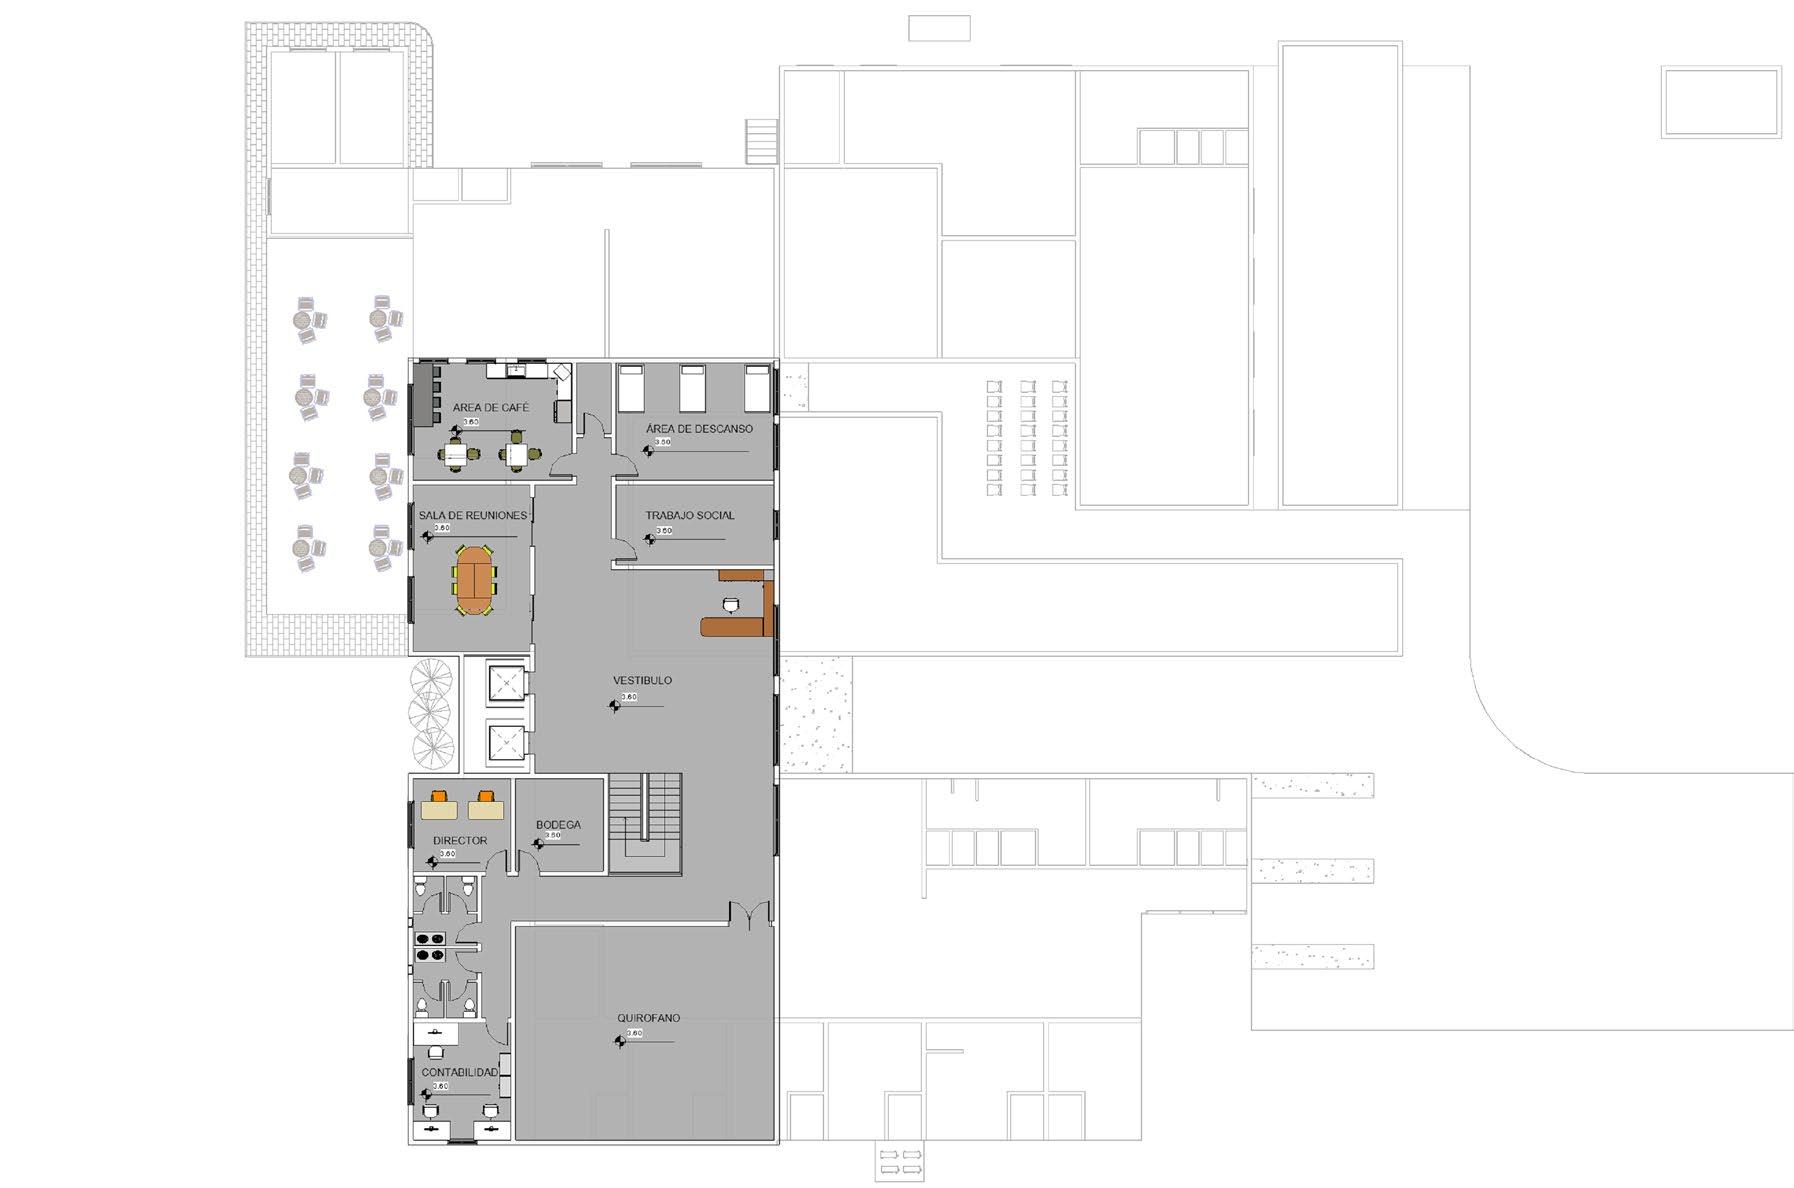

En el segundo nivel se encuentra el quirofano del centro médico y la zona administrativa.

Elemento esencial del área quirúrgica del Centro Médico en el que se lleva a cabo la vigilancia de los pacientes durante el periodo postoperatorio inmediato, y que cuenta con toma de gases, dispositivo de aspiración, punto de luz, monitores de saturación arterial de oxígeno, frecuencia cardiaca y presión arterial.

Habitación la cual tendrán pintura epóxica para una limpieza mejora, y bien iluminada. Espacio amplio para que quepa las máquinas y los materiales.